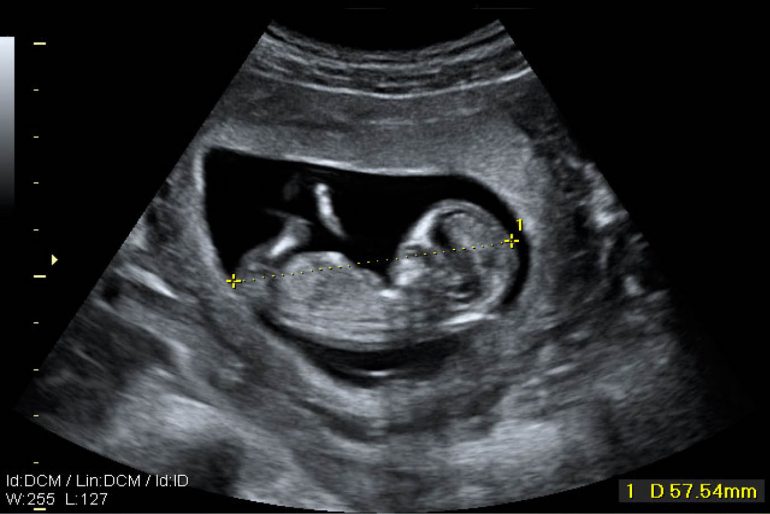

El ultrasonido es totalmente indoloro no tiene efectos secundarios conocidos en las madres o los bebes y se puede llevar a cabo en cualquier etapa del embarazo. Asi que el ultrasonido es el examen de imagen de eleccion para el seguimiento prenatal. El ultrasonido fetal es un estudio que se realiza durante el embarazo para evaluar el desarrollo de tu bebe su anatomia el flujo sanguineo funcionamiento del cordon umbilical la ubicacion de la placenta la cantidad de liquido amniotico y el bienestar general de tu embarazo.

Buscar mellizos o trillizos y examinar la placenta el liquido amniotico y la pelvis. A traves de la piel del abdomen vientre o a traves del interior de la vagina. En definitiva el ultrasonido temprano en el embarazo es un analisis prenatal que usa ondas sonoras para capturar la primera imagen del bebe en el interior del utero materno.

La edad gestacional puede resultar confusa. Una ecografia del embarazo tambien se puede realizar en el segundo y tercer trimestres para. El ultrasonido se basa en el rebote de ondas sonoras sobre el cuerpo del feto en desarrollo.

Determinar la edad el crecimiento la posicion y algunas veces el sexo del bebe. Puede ser que te realicen un ultrasonido en el consultorio de tu medico entre las semanas 6 y 10 para confirmar tu embarazo y comprobar la fecha de la gestacion. Identificar cualquier problema en la forma como el bebe se esta desarrollando.